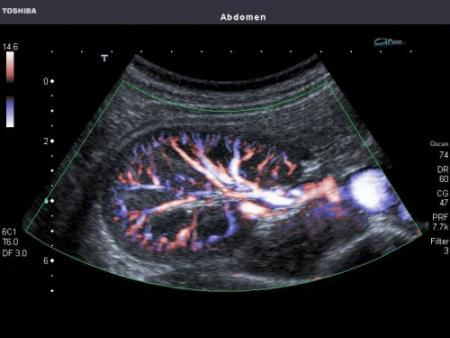

В арсеналі сучасних медиків знаходиться не один вид УЗД. Сьогодні за допомогою цього діагностичного методу можна не тільки виявити наявність каменів або будь-яких новоутворень, оцінити стан паренхіми нирок і їх топографію, а й якість кровообігу. Останні здійснюється за рахунок використання ефекту Доплера, а саме дослідження носить назву УЗДГ судин нирок або доплерографія.

Якщо пацієнту призначено УЗД судин нирок, лікар після здійснення всіх необхідних вимірів і огляду органів на предмет наявності новоутворень і т.д. переводить апарат в інший режим. тепер на екрані монітора фахівець бачить кольорове зображення потоку крові в судинах, мінливий в реальному часі. Завдяки цьому лікар може виявити спазм, тромбоз або звуження постачає нирку артерії.

Допплерография

Допплерографія